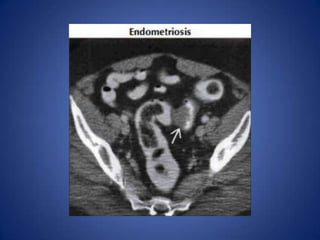

Gynecologic Causes

• Many, including adnexal infection & masses,

torsed ovary, endometriosis, etc.

• Look for evidence of mass &/or inflammation

Gynecologic Causes • Many,including adnexal infection & masses, torsed ovary, endometriosis, etc. • Look for evidence of mass &/or inflammation centered on adnexa, rather than bowel • Uterine Fibroids – May torse , undergo degeneration or infarction, lead to acute pain – Heterogeneous soft tissue masses within enlarged uterus, ± focal calcifications within masses